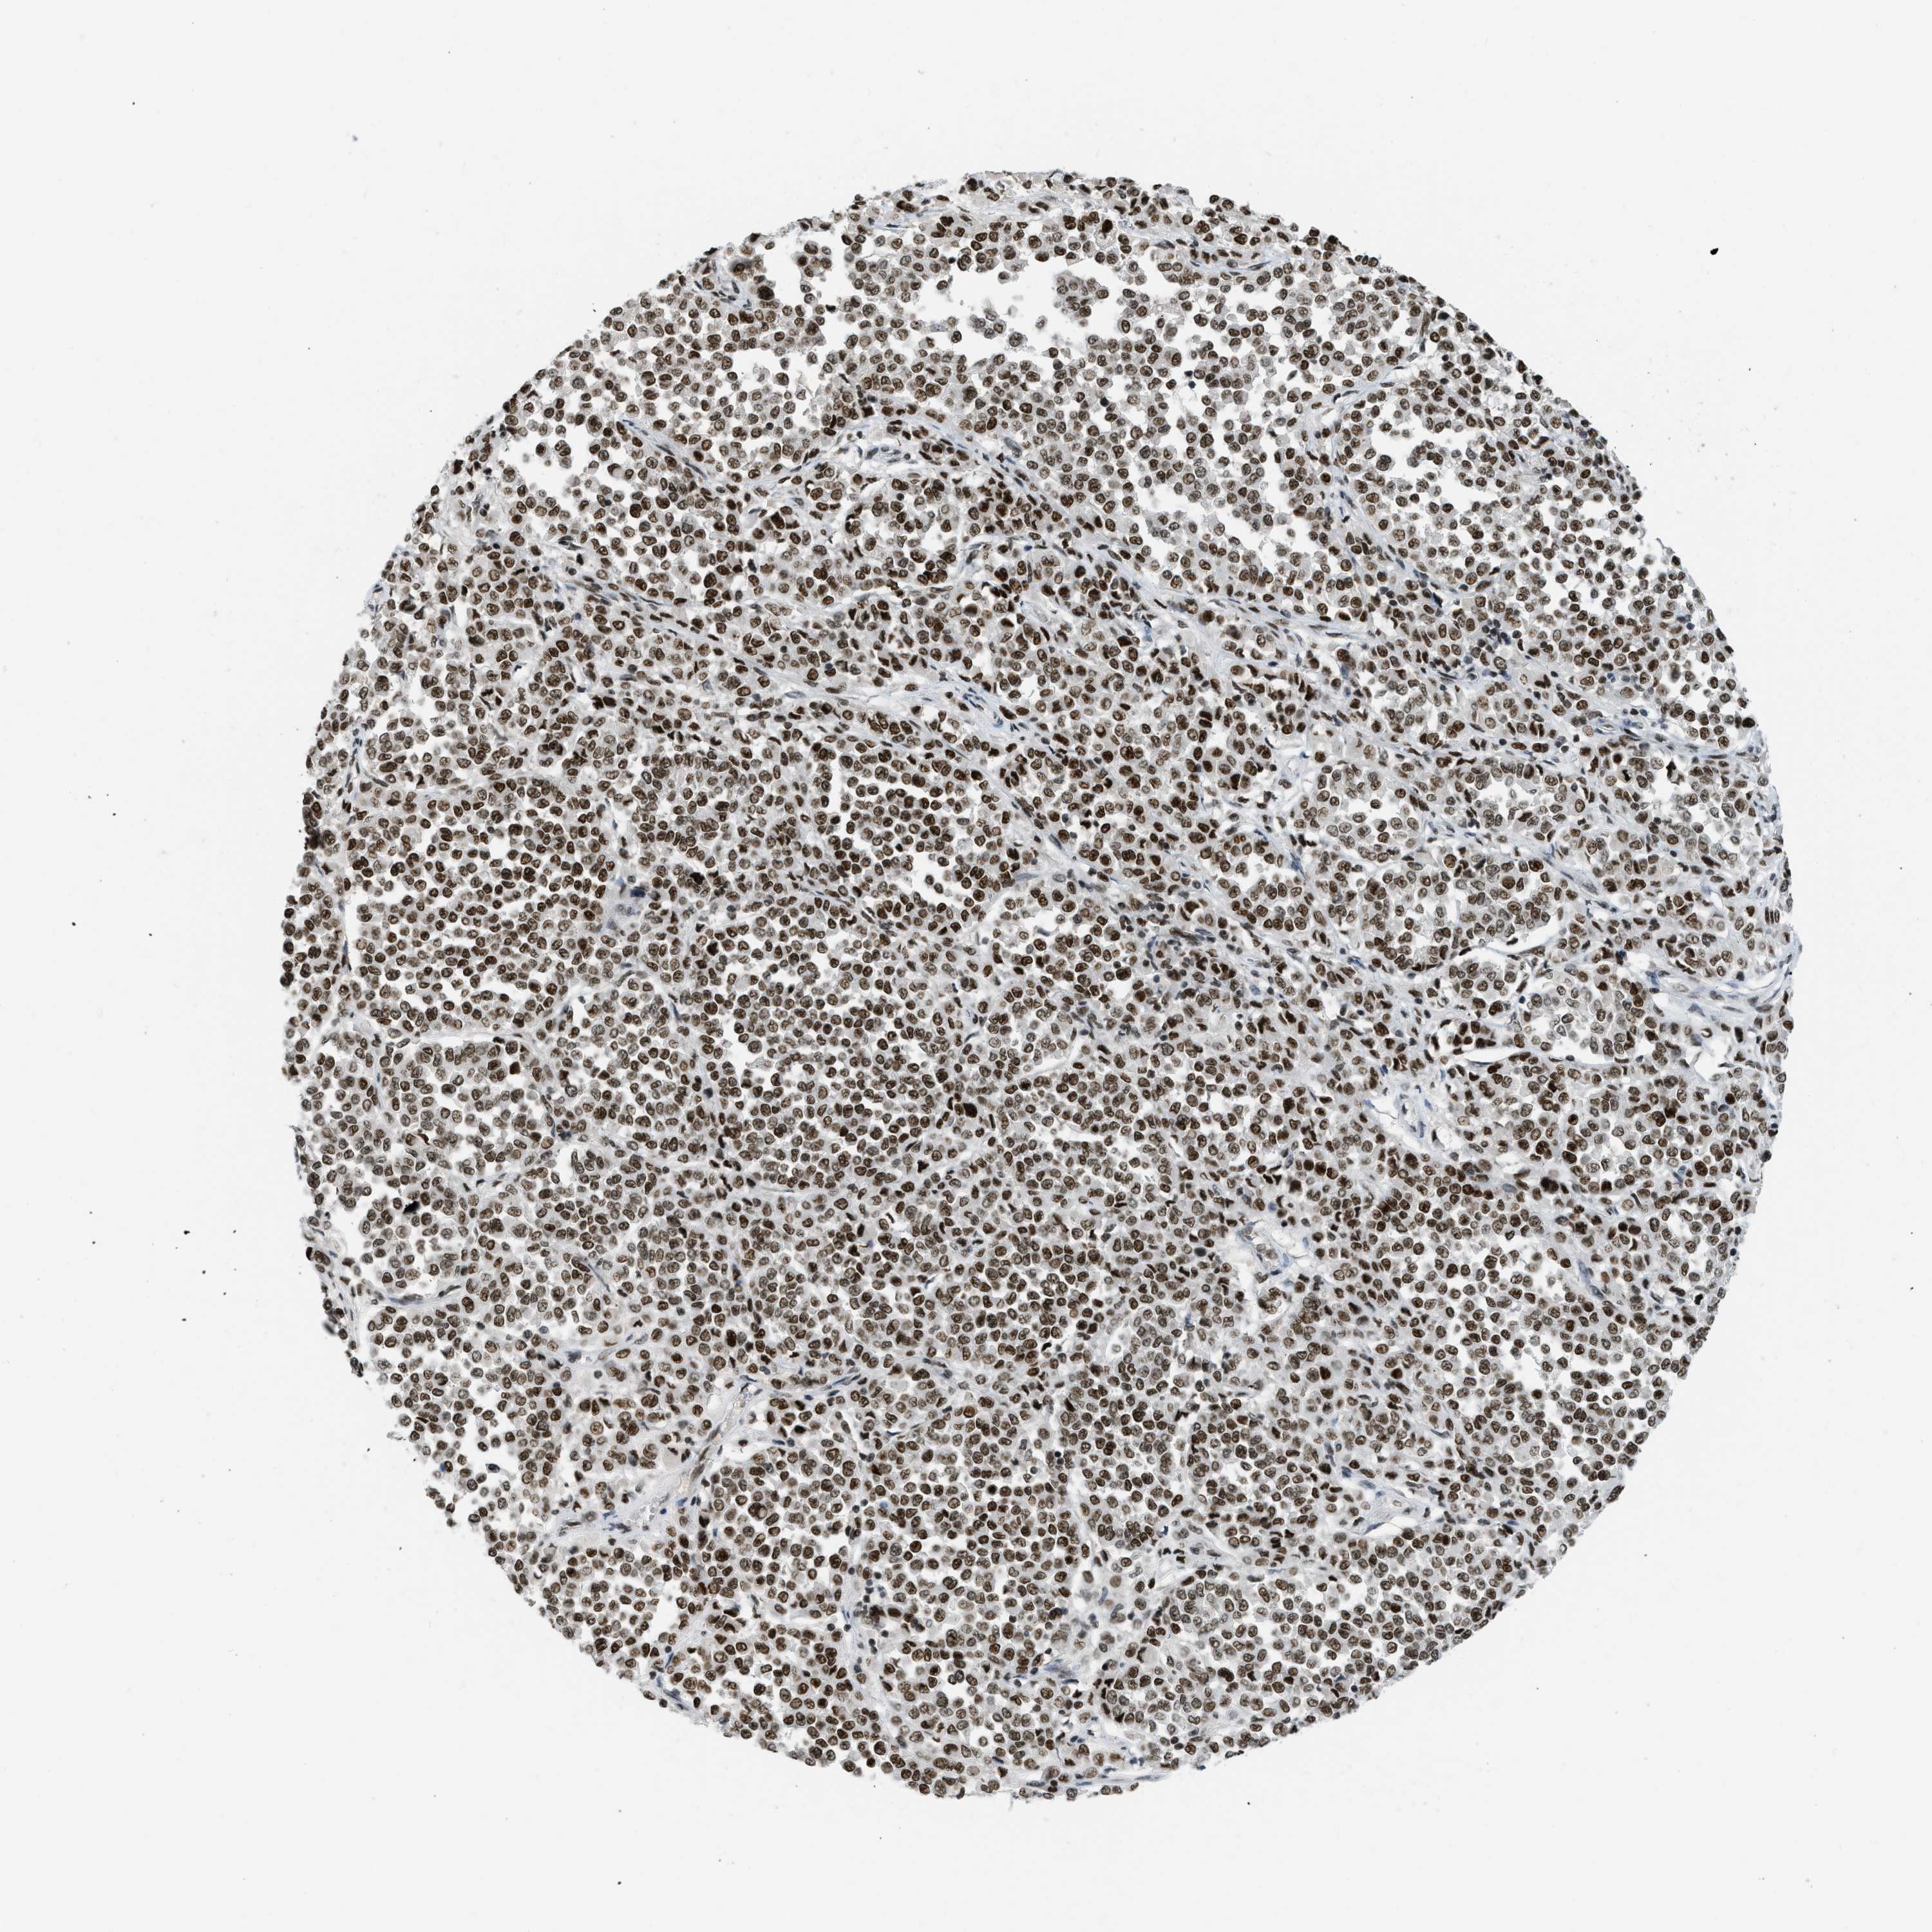

MELANOMA - Protein expressioni

A mouse-over function shows sample information and annotation data. Click on an image to view it in a full screen mode. Samples can be filtered based on level of antibody staining by selecting one or several of the following categories: high, medium, low and not detected. The assay and annotation is described here.

Note that samples used for immunohistochemistry by the Human Protein Atlas do not correspond to samples in the TCGA dataset.

Antibody stainingi

Antibody staining in the annotated cell types in the current human tissue is reported as not detected, low, medium, or high, based on conventional immunohistochemistry profiling in selected tissues. This score is based on the combination of the staining intensity and fraction of stained cells.

Each image is clickable and will lead to virtual microscopy that enables deeper exploration of all samples and also displays staining intensity scores, fraction scores and subcellular localization as well as patient and tissue information for each sample.

Antibody HPA018334

Staining

High

Medium

Low

Not detected

Intensity

Strong

Moderate

Weak

Negative

Quantity

>75%

75%-25%

<25%

None

Location

Nuclear

Cytoplasmic/membranous

Cytoplasmic/membranous,nuclear

Malignant melanoma, NOS